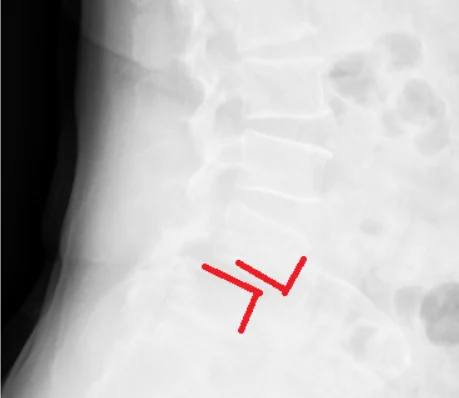

Radiografie din incidența laterală ce demonstrează spondilolisteza L4-L5 la o pacienta în vârstă de 54 ani.